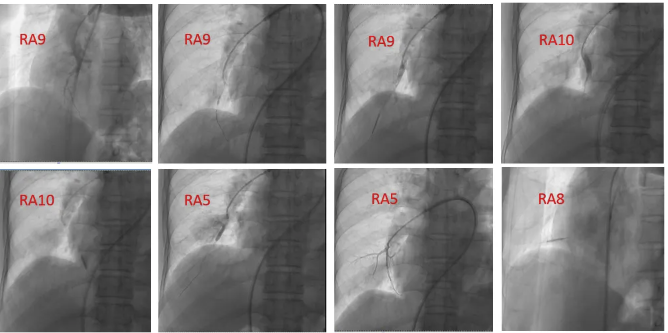

患者CTEPH诊断明确,血栓多为远端病变,有BPA适应征。于2025年3月21日夜间行BPA治疗。共治疗右肺下叶外基底段、后基底段、前基底段肺动脉,右肺中叶内侧段肺动脉4支血管及分支(图8)。整个操作过程顺利,术中无咳嗽、咯血,患者未诉特殊不适,安返病房。返回病房后15分钟左右,病人突发咳嗽、咯血,咯鲜红色血50ml,继而出现氧饱和持续下降至55%,烦躁、呼吸困难,心率114次/分,血压117/70 mmHg。给予止血药物应用,床旁气管镜下可见管腔较多鲜红色血液,以右侧为重,予以充分清理后,患者氧饱和可上升至90%左右。加查血常规,血红蛋白131g/L,相较于术前154g/L,下降23g。3小时后患者再次咯血,伴氧饱和、血压下降,床旁气管镜下可见管腔较多血性不凝固分泌物,予床旁气管插管、呼吸机辅助通气,生命体征平稳,再次复查血红蛋白118g/L。

图8 第一次BPA治疗 2025-3-21